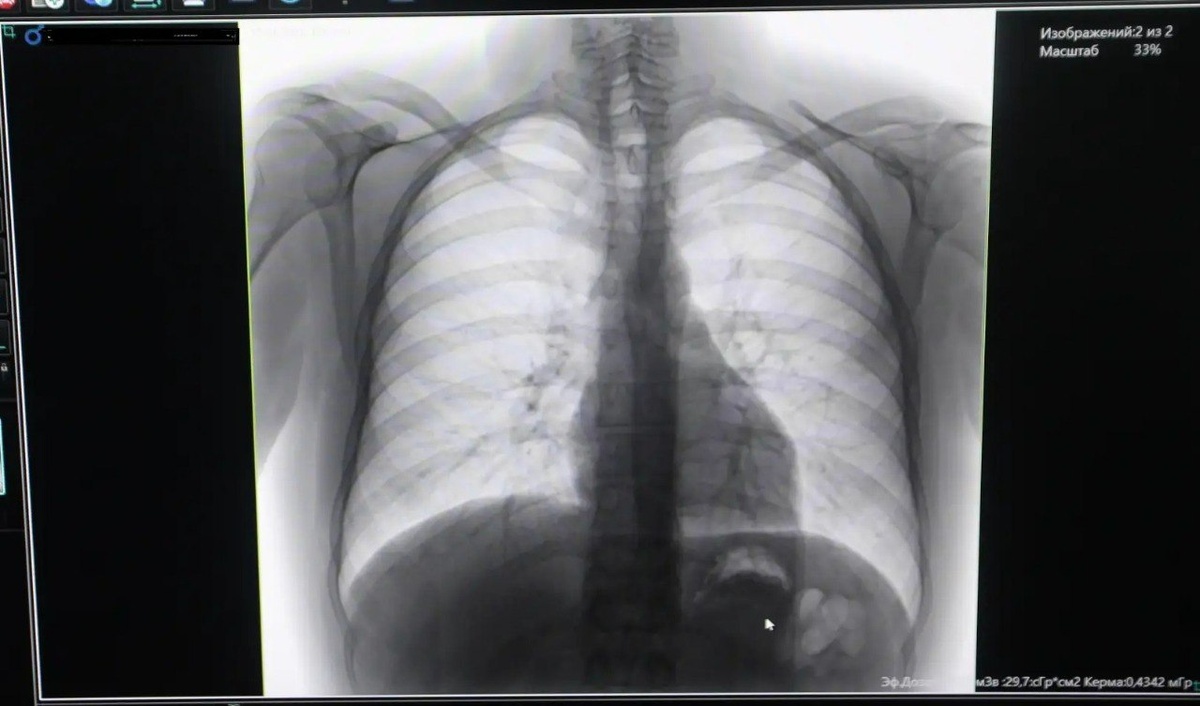

В Чойскую районную больницу поступил новый цифровой флюорограф

Модернизация первичного звена здравоохранения в Республике Алтай продолжается. На этот раз современное диагностическое оборудование получила Чойская больница — закупка проведена в рамках реализации национального проекта «Продолжительная и активная жизнь».

Новый флюорограф позволяет выявлять туберкулез и другие пульмонологические заболевания на самых ранних стадиях, что критически важно для успешного лечения. Как отмечают специалисты, осложнения туберкулеза до сих пор остаются одной из частых причин смерти в мире, поэтому ежегодное прохождение флюорографии рекомендовано всем взрослым.

Главный врач Татьяна Кандаракова подчеркнула: современный цифровой аппарат соответствует всем стандартам и давно ожидался медицинским учреждением. Его внедрение значительно повысит качество диагностики и доступность медицинской помощи для жителей района.